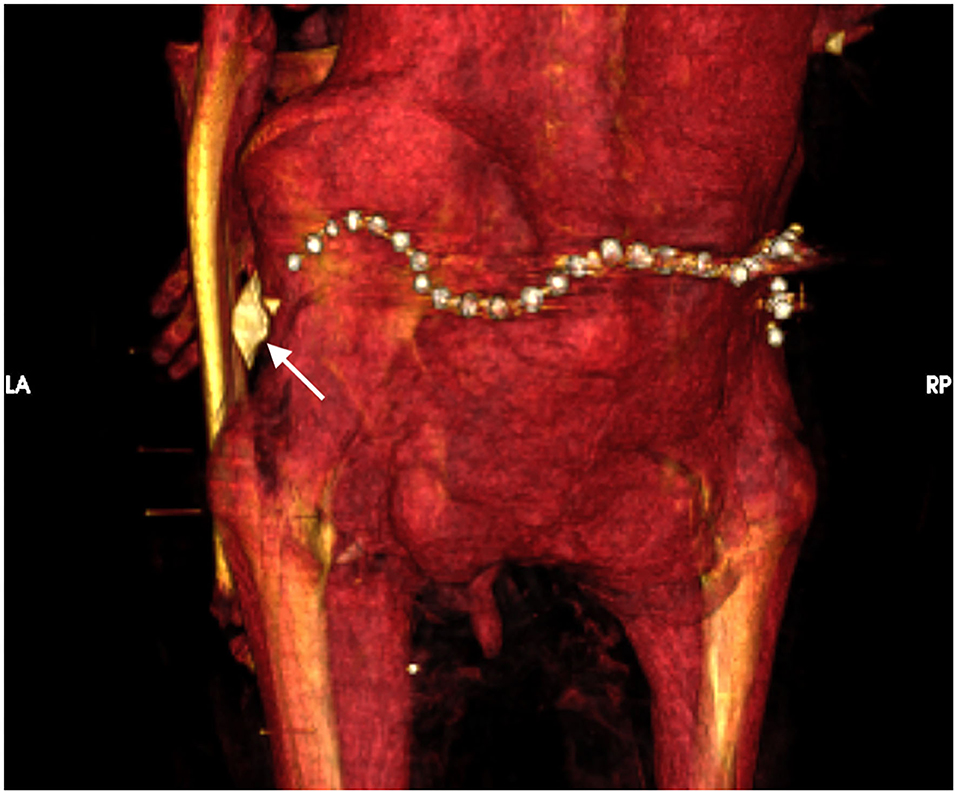

Es por esto que los antropólogos creen que Amenhotep I pudo haber muerto por una infección o virus. Además, estas investigaciones lograron descubrir algunos detalles sobre su momificación y entierro, como que fue el primer faraón en tener los antebrazos cruzados sobre el pecho y que, extrañamente, no se le extirpó el cerebro, algo normal en el ritual de momificación.

Por otra parte, supieron que sacerdotes de la dinastía XXI, la cual gobernó unos cuatro siglos después de su muerte, lo repararon, ya que posiblemente fue víctima de ladrones de tumbas. Sí, por ejemplo, se dieron cuenta que fijaron su cabeza y el cuello, los cuales estaban desprendidos del cuerpo.

Por último, la doctora señaló que el faraón lleva 30 amuletos y un cinturón dorado con cuentas de oro, los cuales no se los quitaron sacerdotes para otros faraones, algo que llegó a pensarse pero que ahora ya se descartó.